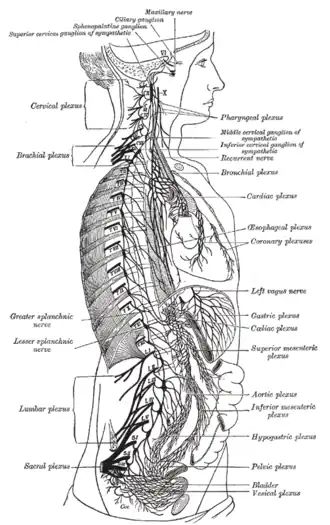

The right sympathetic chain and its connections with the thoracic, abdominal, and pelvic plexuses

The right sympathetic chain and its connections with the thoracic, abdominal, and pelvic plexuses -

The vagus nerve, also known as the tenth cranial nerve (CN X), plays a crucial role in the autonomic nervous system, which is responsible for regulating involuntary functions within the human body. This nerve carries both sensory and motor fibers and serves as a major pathway that connects the brain to various organs, including the heart, lungs, and digestive tract. As a key part of the parasympathetic nervous system, the vagus nerve helps regulate essential involuntary functions like heart rate, breathing, and digestion. By controlling these processes, the vagus nerve contributes to the body's "rest and digest" response, helping to calm the body after stress, lower heart rate, improve digestion, and maintain homeostasis.

Structure

Upon leaving the medulla oblongata between the olive and the inferior cerebellar peduncle, the vagus nerve extends through the jugular foramen, then passes into the carotid sheath between the internal carotid artery and the internal jugular vein down to the neck, chest, and abdomen, where it contributes to the innervation of the viscera, reaching all the way to the colon. Besides giving some output to various organs, the vagus nerve comprises between 80% and 90% of afferent nerve fibers conveying sensory information about the state of the body's organs to the central nervous system.[4]

The right and left vagus nerves descend from the cranial vault through the jugular foramina,[5] penetrating the carotid sheath between the internal and external carotid arteries, then passing posterolateral to the common carotid artery. The cell bodies of visceral afferent fibers of the vagus nerve are located bilaterally in the inferior ganglion of the vagus nerve (nodose ganglia).The vagus runs parallel to the common carotid artery and internal jugular vein inside the carotid sheath.

Right Vagus Nerve: The right vagus nerve gives rise to the right recurrent laryngeal nerve, which hooks around the right subclavian artery and ascends into the neck between the trachea and esophagus. The right vagus then crosses anterior to the right subclavian artery, runs posterior to the superior vena cava, descends posterior to the right main bronchus, and contributes to cardiac, pulmonary, and esophageal plexuses. It forms the posterior vagal trunk at the lower part of the esophagus and passes through the diaphragm to enter the abdomen through the esophageal hiatus.

Left Vagus Nerve: The left vagus nerve enters the thorax between left common carotid artery and left subclavian artery and descends on the aortic arch. It gives rise to the left recurrent laryngeal nerve, which hooks around the aortic arch to the left of the ligamentum arteriosum and ascends between the trachea and esophagus. The left vagus further gives off thoracic cardiac branches, breaks up into the pulmonary plexus, continues into the esophageal plexus, and enters the abdomen as the anterior vagal trunk by way of the esophageal hiatus of the diaphragm.

The vagus nerve supplies motor parasympathetic fibers to all the organs (except the adrenal glands) from the neck down to the second segment of the transverse colon. The vagus also controls a few skeletal muscles, including:

This means that the vagus nerve is responsible for such varied tasks as heart rate, gastrointestinal peristalsis, sweating, and quite a few muscle movements in the mouth, including speech (via the recurrent laryngeal nerve). It also has some afferent fibers that innervate the inner (canal) portion of the outer ear (via the auricular branch, also known as Arnold's or Alderman's nerve) and part of the meninges.[10] The vagus nerve is also responsible for regulating inflammation in the body, via the inflammatory reflex.[11]